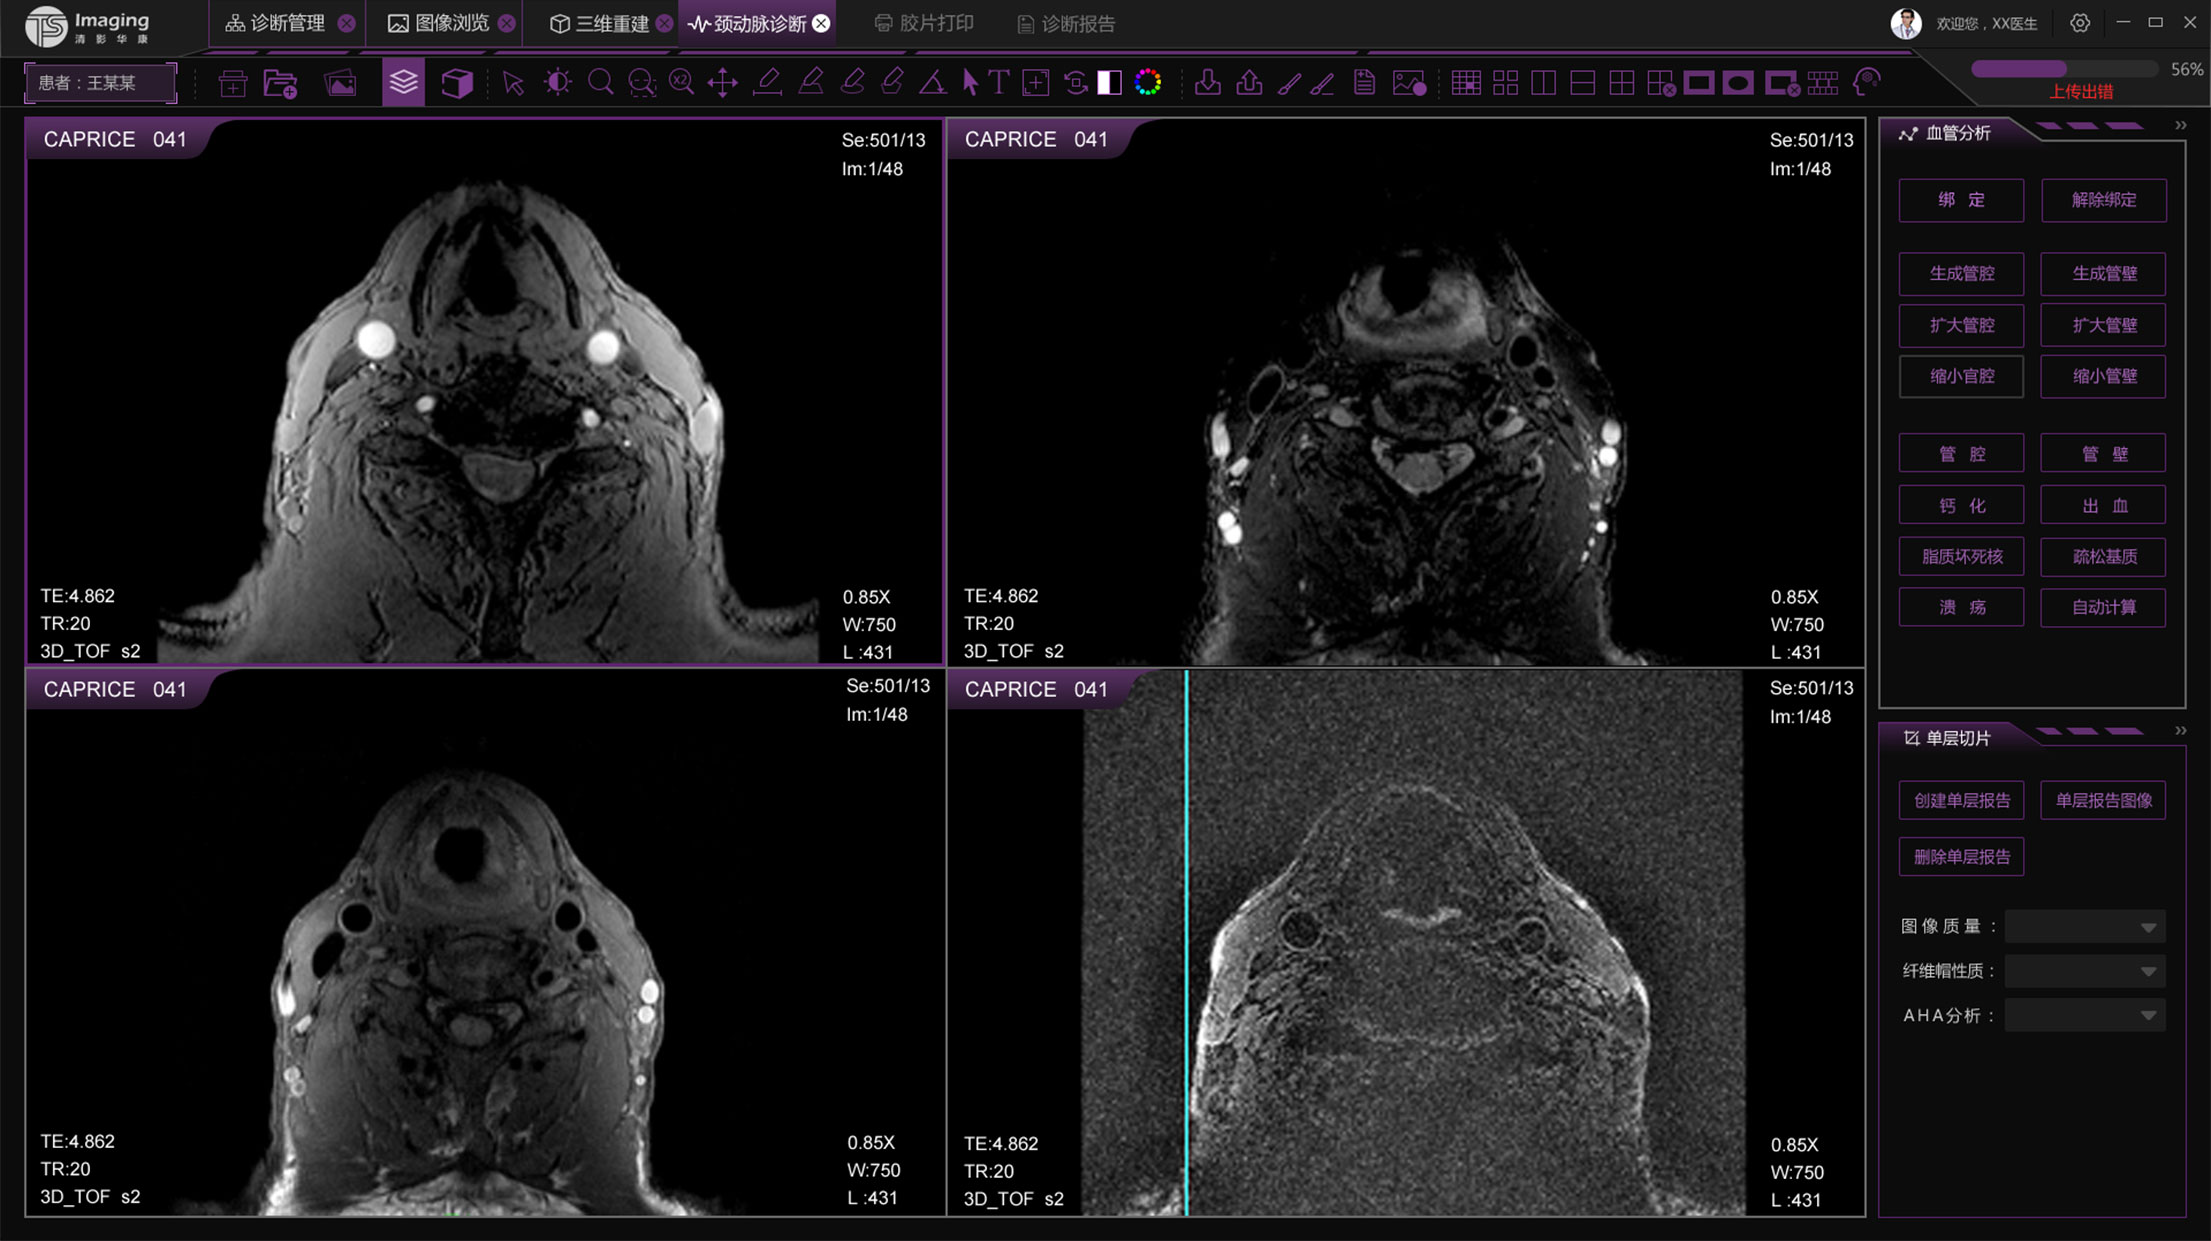

頸動(dòng)脈診斷頁(yè)面

頸動(dòng)脈診斷頁(yè)面整體布局和三維重建比較相似,最大的區(qū)別是右側(cè)的操作區(qū)域,血管分析都為按鍵操作,通過(guò)間隔的大小分成三部分。單層切片除了按鍵還有下拉菜單的操作。

頸動(dòng)脈診斷原型